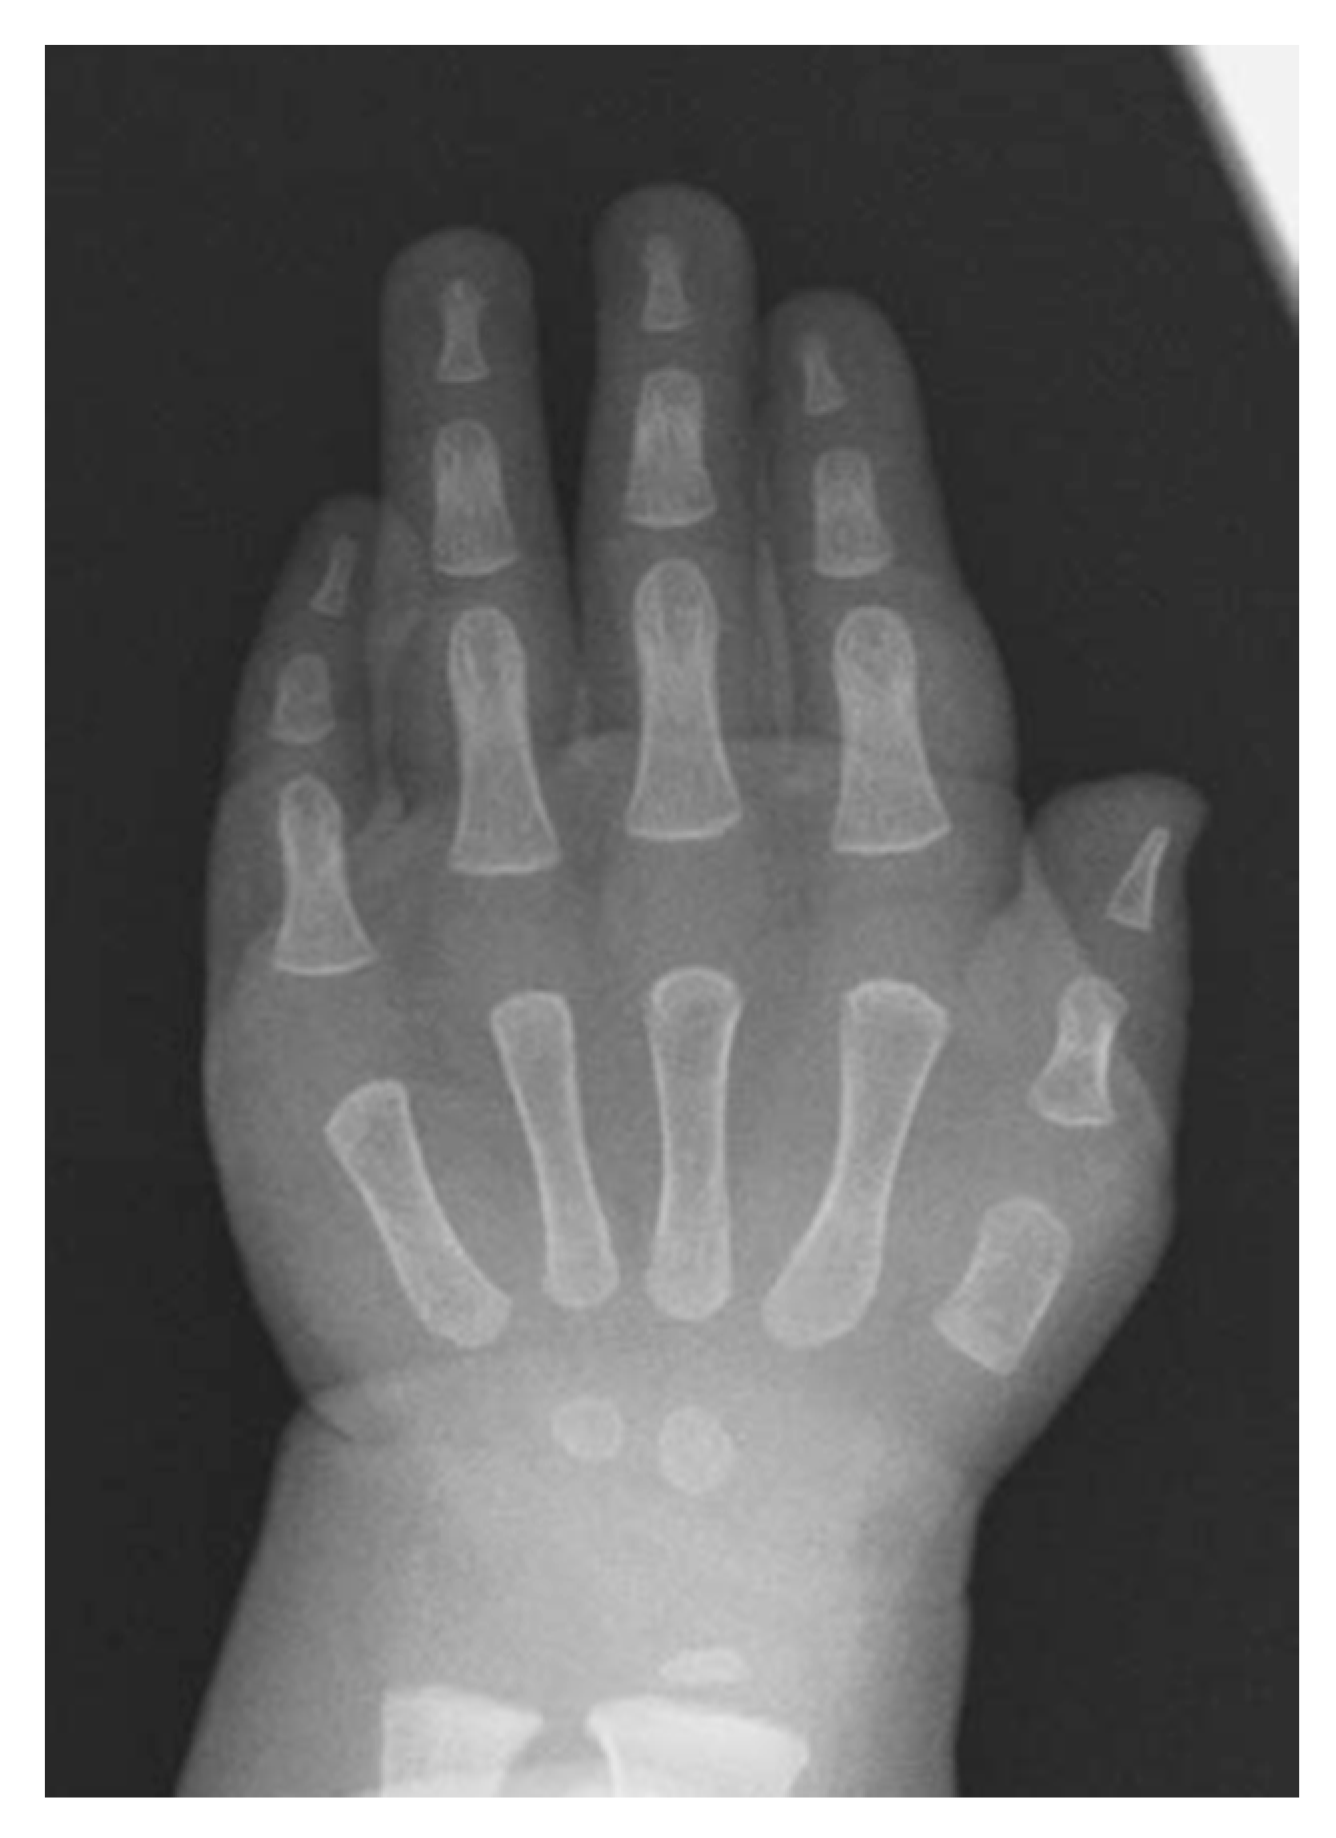

- Mishima, K.; Kitoh, H.; Haag, N.; Nakashima, Y.; Kamizono, J.; Katagiri, T.; Susami, T.; Matsushita, M.; Ishiguro, N. Radiographic characteristics of the hand and cervical spine in fibrodysplasia ossificans progressive. Intractable Rare Dis. Res. 2014, 3, 46–51. [Google Scholar] [CrossRef]

- Oberg, K.C. Review of the molecular development of the thumb: Digit primera. Clin. Orthop. Relat. Res. 2014, 472, 1101–1105. [Google Scholar] [CrossRef][Green Version]

- Deschamps, J. Tailored Hox gene transcription and the making of the thumb. Genes Dev. 2008, 22, 293–296. [Google Scholar] [CrossRef] [PubMed][Green Version]

- Li, X.; Nie, S.; Chang, C.; Qiu, T.; Cao, X. Smads oppose Hox transcriptional activities. Exp. Cell Res. 2006, 312, 854–864. [Google Scholar] [CrossRef] [PubMed]